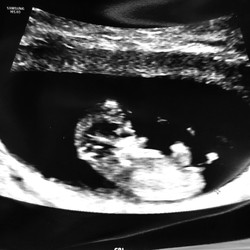

Ja, begrijp ik.. ik heb nu gelukkig wel wat meer vertrouwen al dan de vorige keer ..omdat alle tekenen er eigenlijk wel zijn en ik me belabberd voel nu in week 10 😅😁..maar het blijft spannend ..morgen de 2e echo 🙏🏻